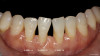

A determination of parameters for patient selection requires an examination of the classes of marginal tissue recession as defined by Dr. P.D. Miller. A conservative approach to treating Class III and Class IV recession defects, per Miller, is possible utilizing a combination of pink and white Giomer Technology restorative materials. A Miller Class III features marginal tissue recession that extends to or beyond the mucogingival junction, with periodontal attachment loss in the interdental area or malpositioning of teeth, and a Miller Class IV features marginal tissue recession that extends to or beyond the mucogingival junction, with severe bone or soft tissue loss in the interdental area and/or malpositioning of teeth1 (Figure 1). Recommended parameters for proper patient selection relating to this type of procedure generally include the existence of Class III and/or Class IV recession.

The patient's Class I areas would have been easily graftable, with marginal tissue recession that did not extend to the mucogingival junction. The schematic drawing in Figure 1 shows little classic recession defects that are Class III, with marginal tissue recession that extends to or beyond the mucogingival junction with no attachment loss of bone or soft tissue in the interdental area.